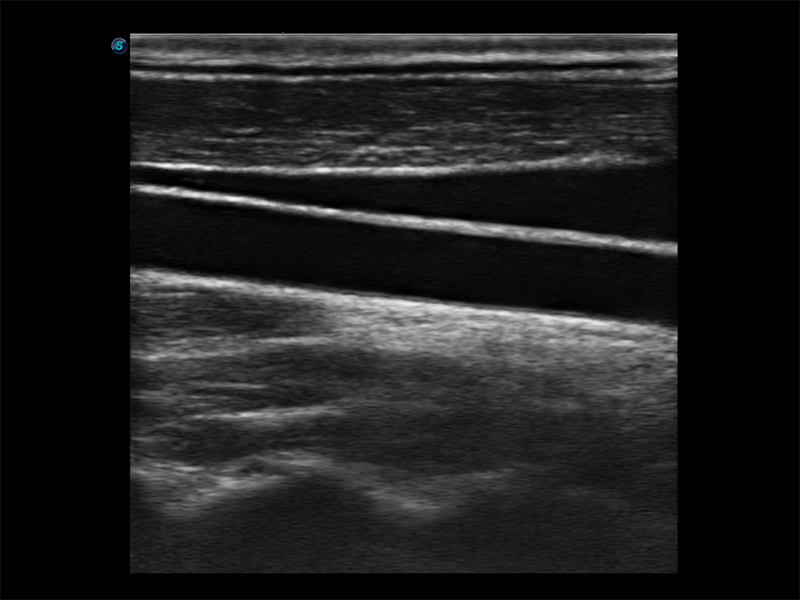

Funkcja B Steer dostępna dla głowic liniowych

Obrazowanie szerokokątne – powiększony obszar obrazu